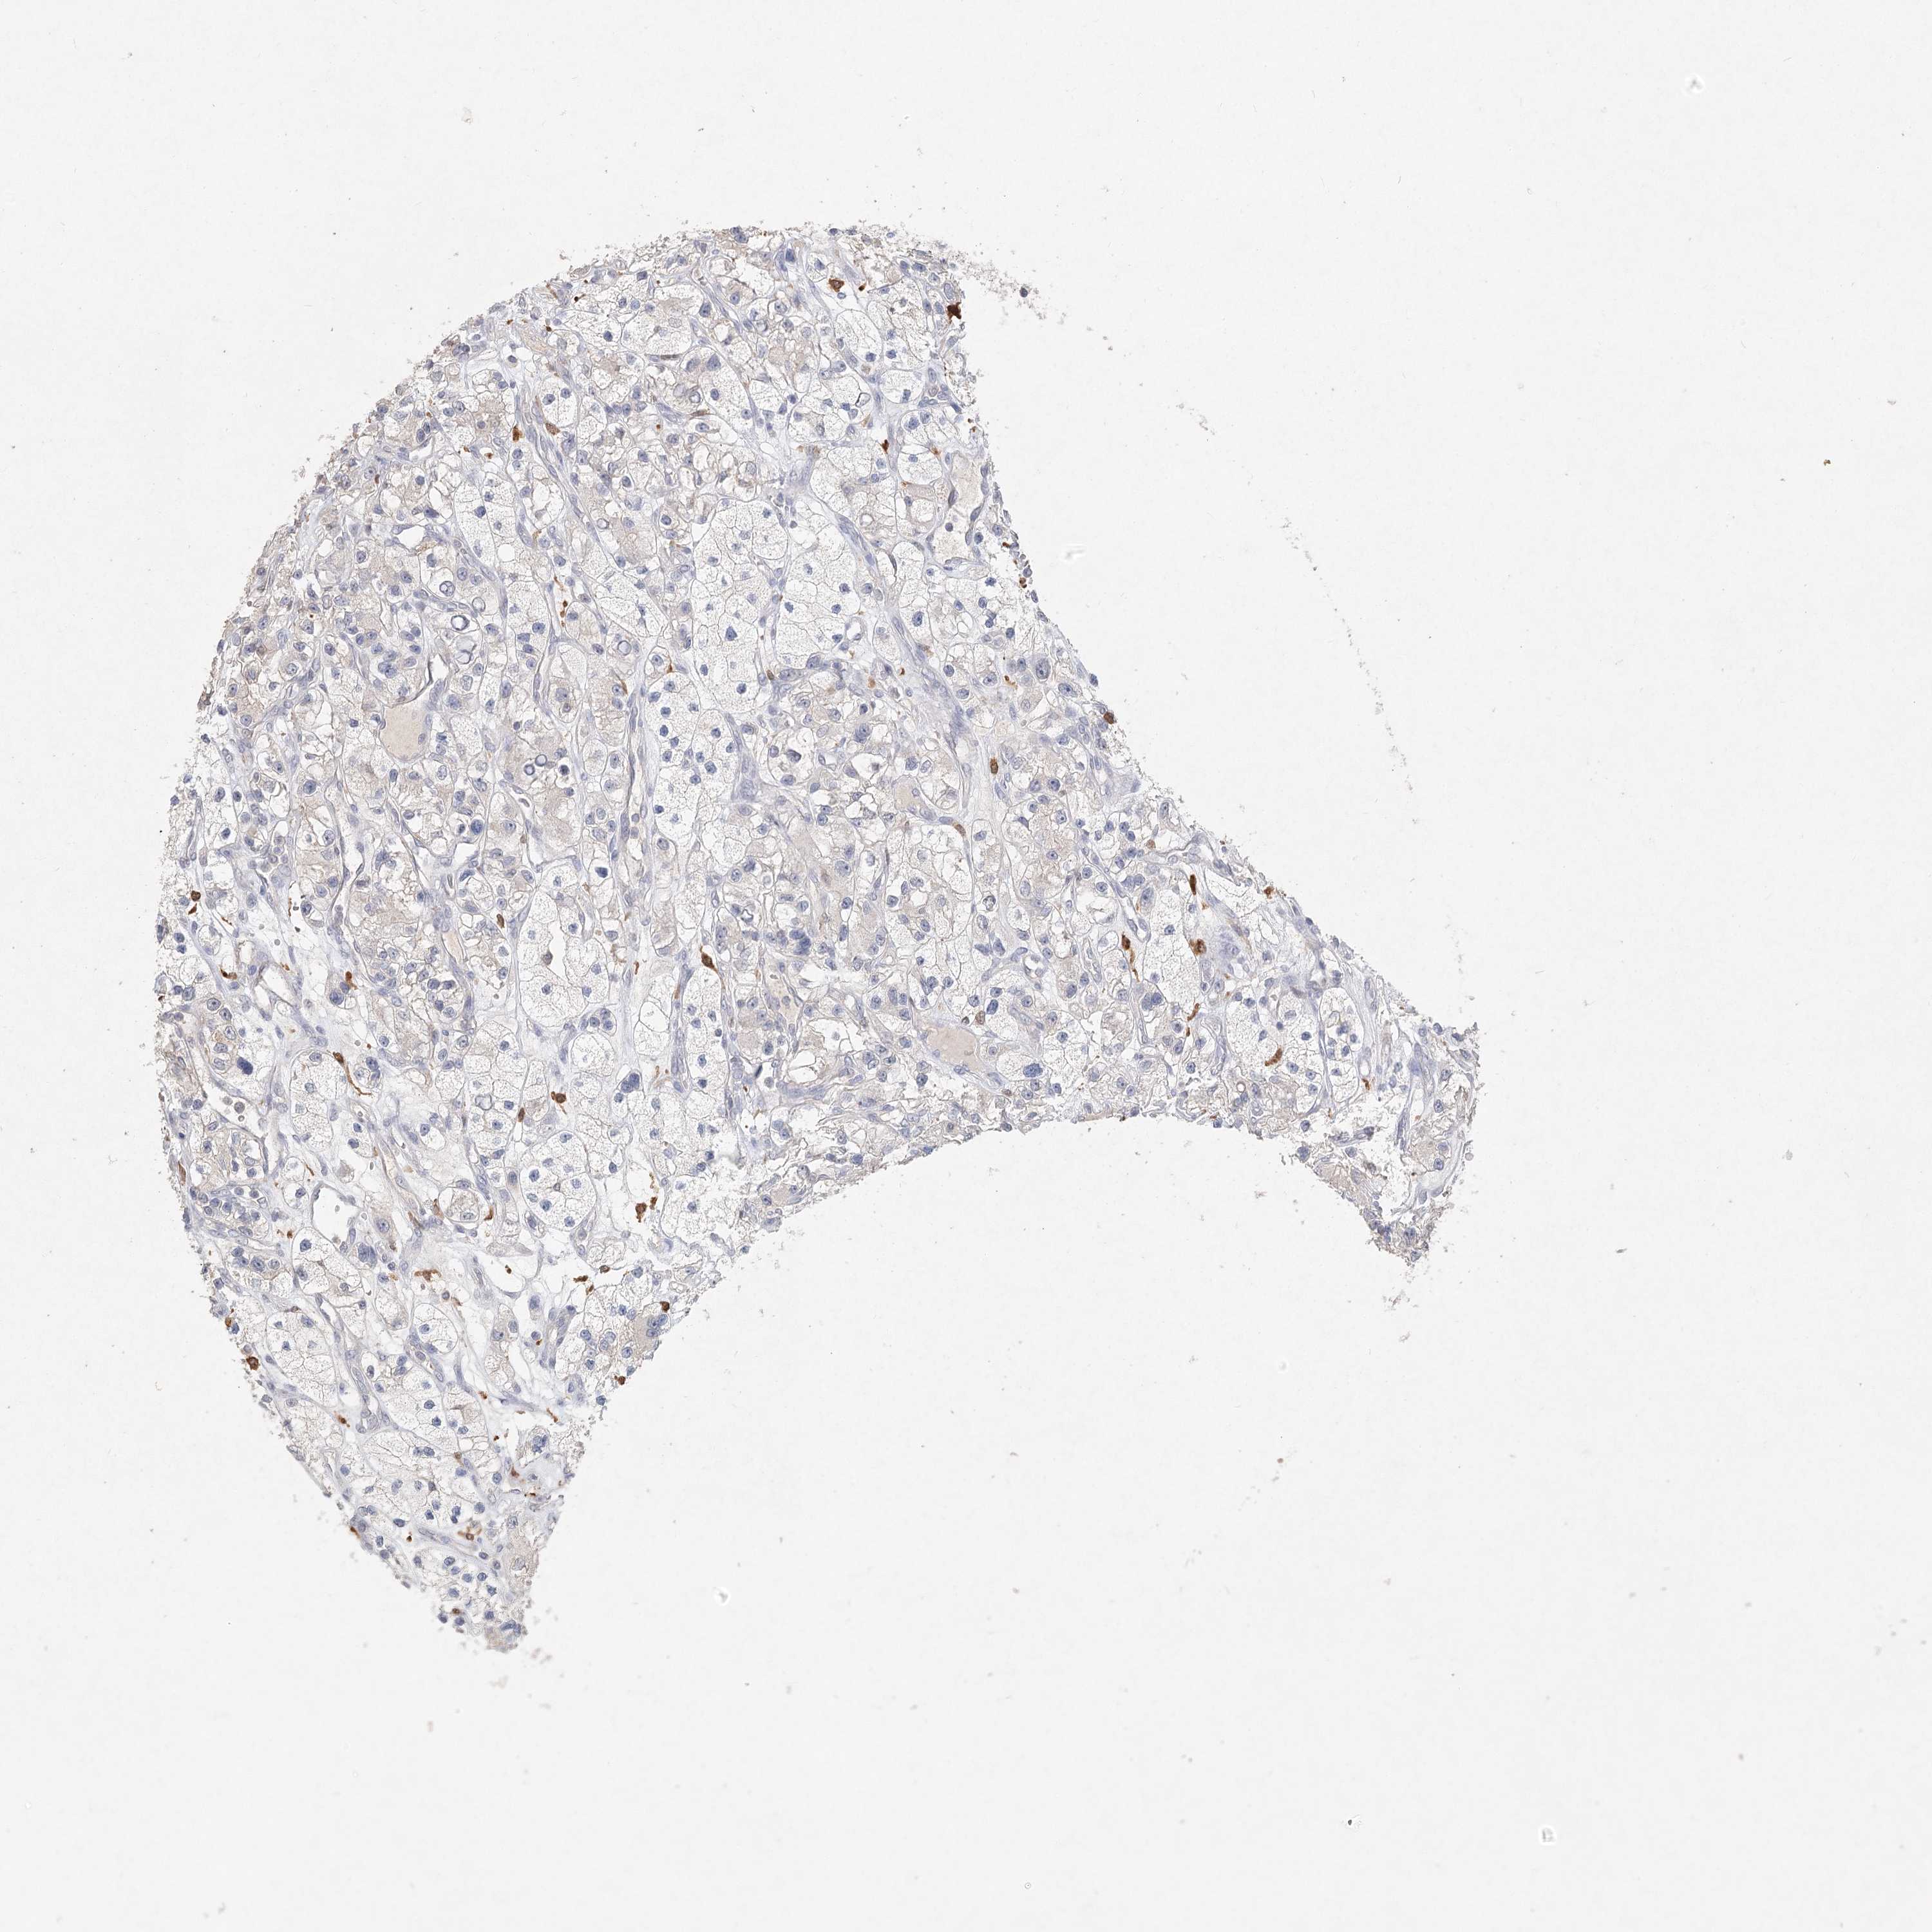

CANCER RENAL CANCER Show tissue menu

KICH TCGA KIRC TCGA KIRC VALIDATION KIRP TCGA PROTEIN RCC CPTAC PROTEIN EXPRESSION